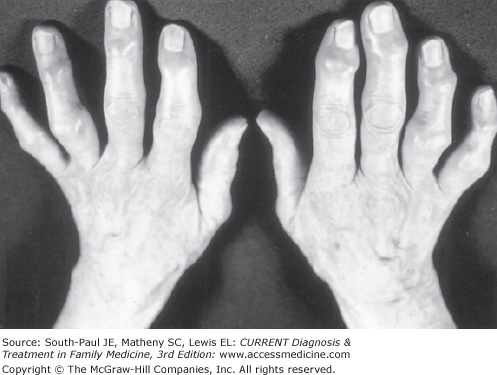

Симптомы и лечение остеоартроза узелков Гебердена: фотогалерея